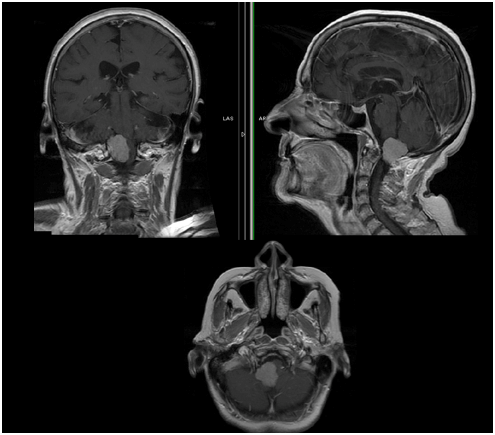

枕骨大孔区脑膜瘤由于其位置、与神经轴和下颅神经以及与椎动脉(VA)和分支的密切关系,无疑是一种具挑战性的病变。此外,当发现这些肿瘤时,由于其生长速度慢、进展缓慢、诊断困难,从一个症状开始间隔时间长,在这个水平上蛛网膜下腔宽,这些肿瘤往往很大。众所周知,其他几个因素与较高的发病率相关,如肿瘤位置、肿瘤侵袭性、硬膜外扩张、VA包膜、蛛网膜鞘缺失以及复发病灶的粘连。

在巴特朗菲教授一篇关于枕骨大孔腹外侧脑膜瘤手术切除的论文中很好地证实了显微外科手术切除腹侧及腹外侧大孔脑膜瘤是一种顺利、值得的手术方法。该论文报告了19例经背外侧枕下入路手术的大孔脑膜瘤患者的经验,每一个病例中都实现了肿瘤的完全切除,通过案例术后效果跟踪,巴特朗菲教授强调了这些病变的显微外科手术切除意义包括两个重要方面,一是基于每个患者的显微解剖细节能够有细致和个性化的术前手术方案定制,这使得手术的顺利性和准确度大大提高,二是在过去的5年里,这些病例都没有死亡,也没有神经并发症,这种效果不论是对于医生还是对于患者来说,无疑都是振奋人心的。